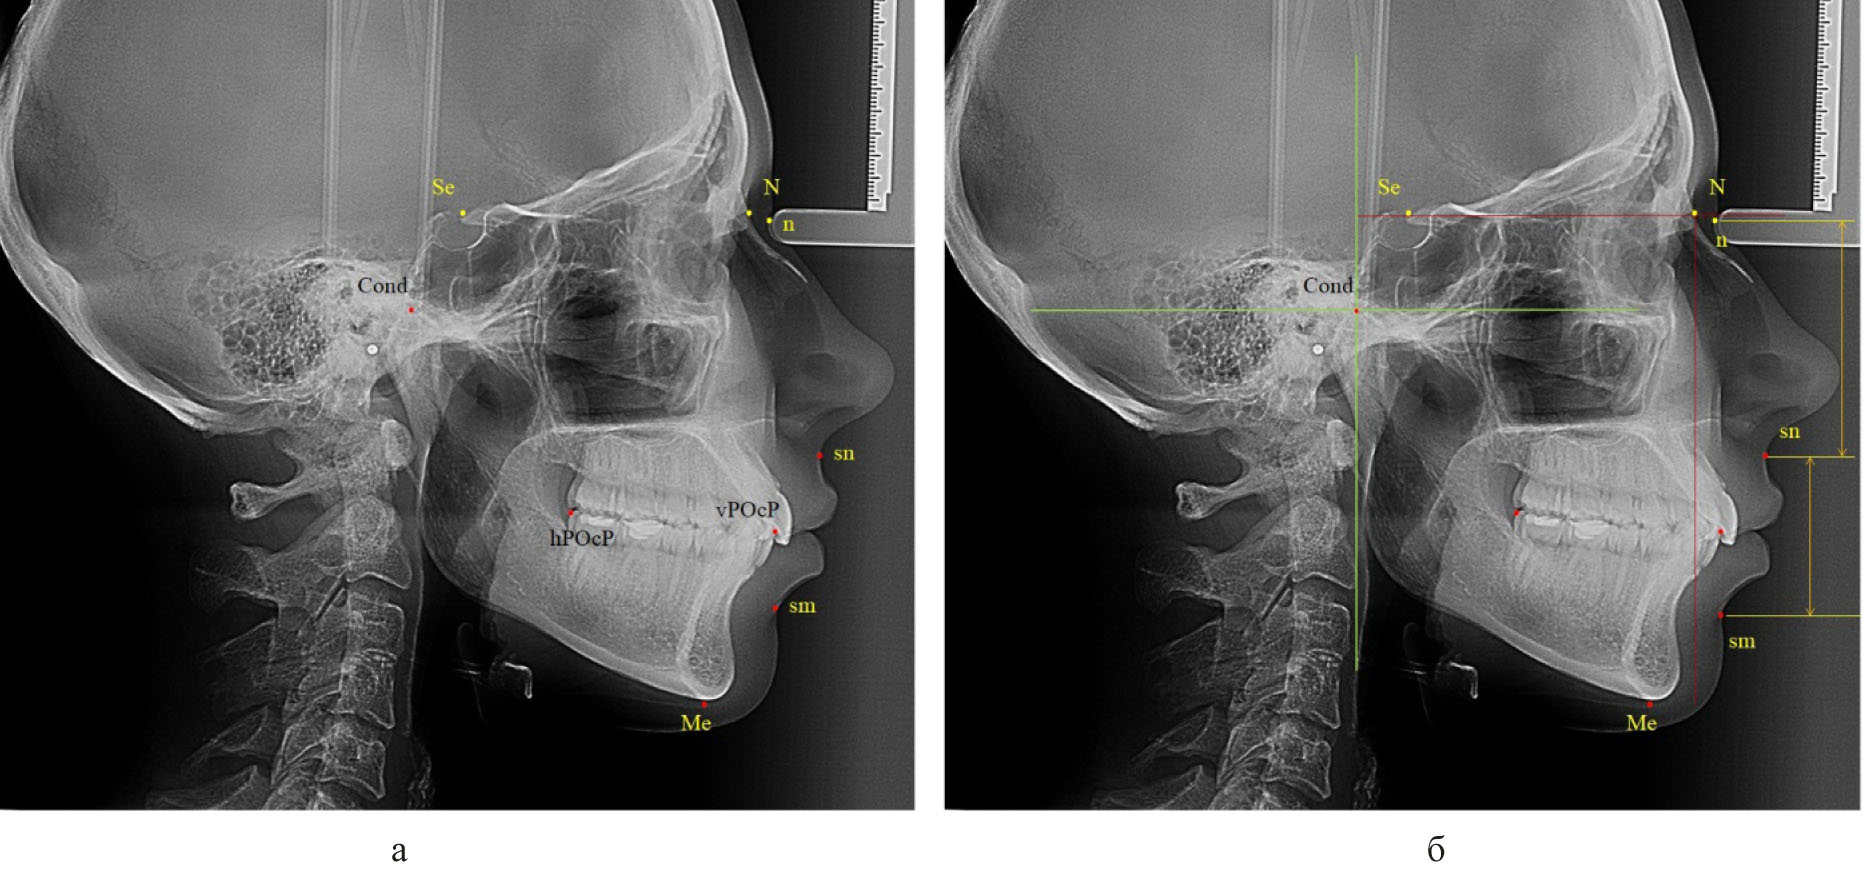

Для оценки типа роста использовали наиболее удобный показатель, такой как угол нижней челюсти. Основные точки для построения угла были наиболее выступающие части ветви, обозначаемые литерами (Ar) и (T1), и тела челюсти (T2) и (Me). Линии, соединяющие отмеченные точки, определяли угол нижней челюсти и положение конструктивной точки «Go» (рис. 2).

Рис. 2. Точки (а) и линии (б) для анализа угла нижней челюсти

Нейтральный тип роста и нижнечелюстного угла определялся при его величине от 119 до 123 градусов. Увеличение размеров свидетельствовало о принадлежности к вертикальному типу, а уменьшение – к горизонтальному типу.